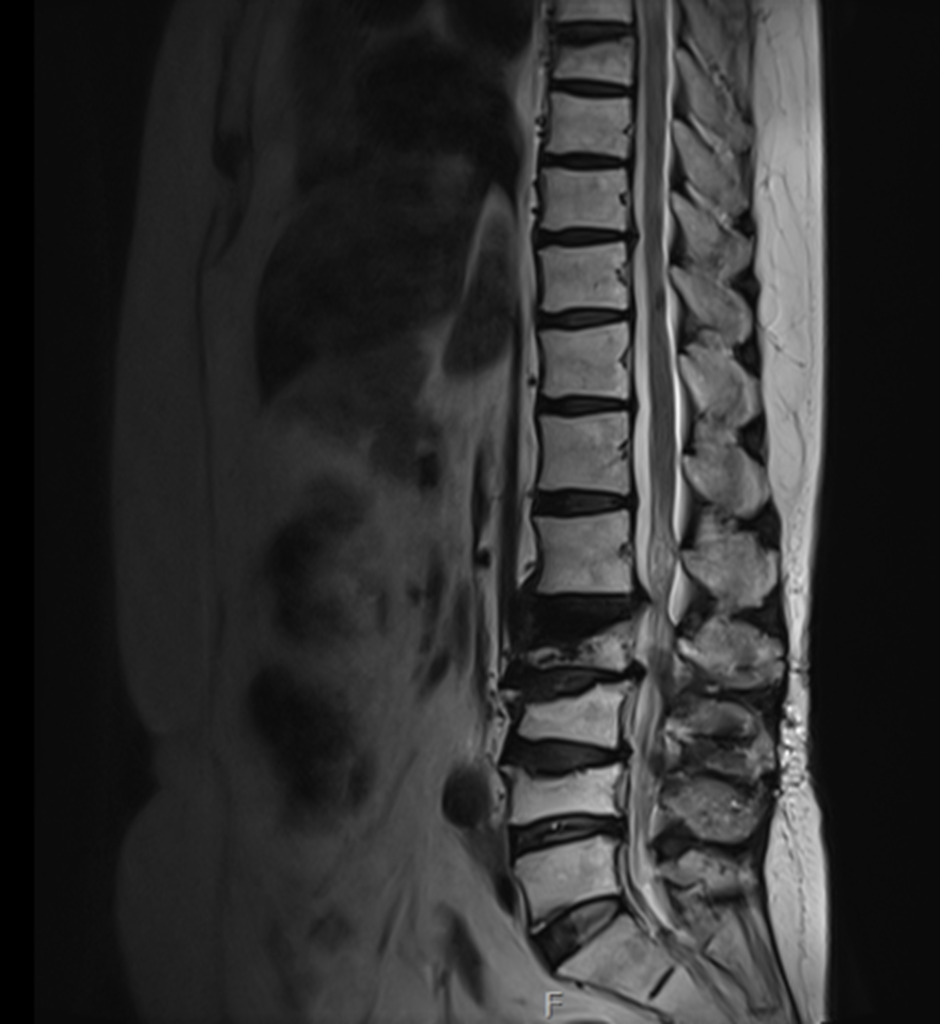

임상 소견만으로는 확신할 수 없어서

뇌 MRI와 MRA를 시행했습니다.

파킨슨병 자체는 MRI로 직접 진단할 수 있는 질환은 아니지만,

다른 원인들을 배제하는 게 중요하거든요.

그림4.png 촬영 일시: 2024.10.11

뇌경색이나 뇌출혈, 뇌종양 등

다른 심각한 뇌 질환들이

비슷한 증상을 일으킬 수 있어서요.

검사 결과 다행히 구조적인 이상은 없었고,

임상 증상과 신경학적 진찰 소견을 종합해서

파킨슨병으로 진단할 수 있었습니다.